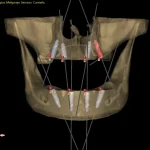

This is the most important advantage. By planning in 3D, the surgeon can "see" through the bone and gum.

- Safety: It allows for the identification and marking of vital anatomical structures (like the inferior alveolar nerve or the maxillary sinus). The surgical guide ensures the implant is placed at a safe distance from these structures, drastically reducing the risk of complications such as paresthesia (numbness of the lip) or sinusitis.

- Precision: It eliminates the guesswork and variability of freehand surgery. The implant is placed with submillimetric accuracy, exactly where it was planned.